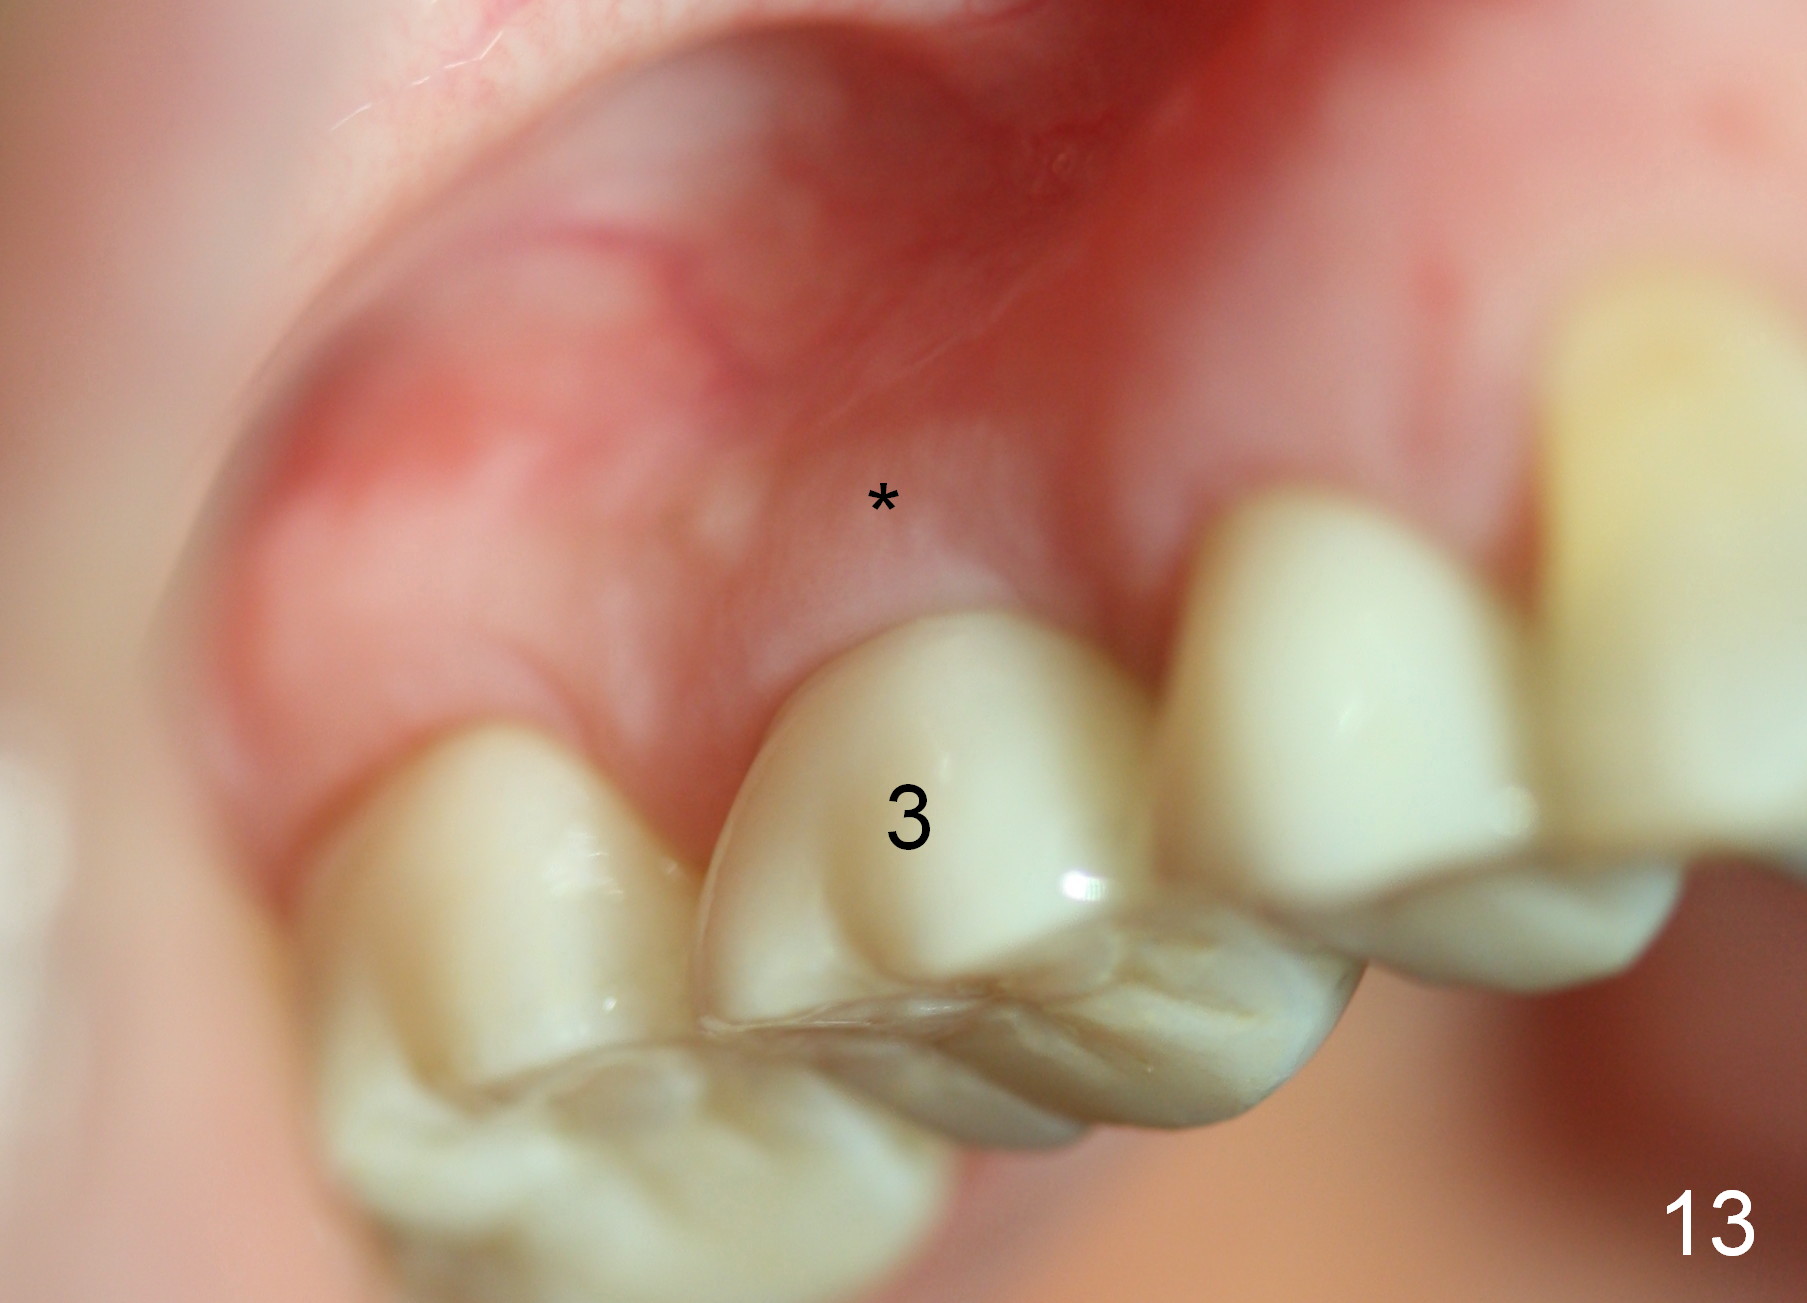

The bone density (Fig.1 white *) at the edentulous area (#3) is lower than that at the dentulous one (black *, 50 year-old man). The buccal plate is also atrophic and concave (Fig.2,3 arrowheads). A series of bone expanders are used to form osteotomy (following 1.6 mm pilot drill) at the depth of 14 mm (Fig.3 E 3.0 mm in diameter). When the last expander (4.3 mm) is removed from the osteotomy, the buccal plate appears to have been moved buccally (Fig.5 arrowheads). A 5.3x14 mm submerged implant (Fig.6 I) is placed with insertion torque >35 Ncm. The buccal plate seems to improve following placement of an 8.2 mm healing abutment and suturing (Fig.7). No bone graft is used. The buccal plate remains normal 12 days postop (Fig.8). It is slightly concave 3 months postop (Fig.9) with minimal bone resorption at the crest (Fig.10 (H: healing abutment),11 (A: cemented abutment). Nine months post cementation (12 months postop), bone resorption at the crest remains minimal (Fig.12) while the buccal plate (Fig.13 *) at #3 remains strong. Bone loss appears not to get worse 22 months post cementation (Fig.14). Soft and hard tissues remain healthy around the implant crown 3 years (Fig.15) and 3.5 years (Fig.16,17) post cementation.

In brief, bone expanders or osteotomes can be used for bone expansion and condensation to improve primary stability of implant placement. No bone graft appears to be needed. The buccal concavity remains minimal 6 years post cementation (Fig.18). In fact he is a bruxer with torus palatinus (Fig.19). The bridge of #9-11 is loose because of subgingival fracture of the abutment of #11 for 2.5 years (Fig.20).